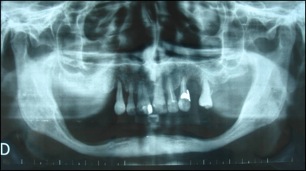

Cette greffe peut être posée soit en apposition (en plaque maintenue par des vis) au maxillaire ou à la mandibule, comme ceci :